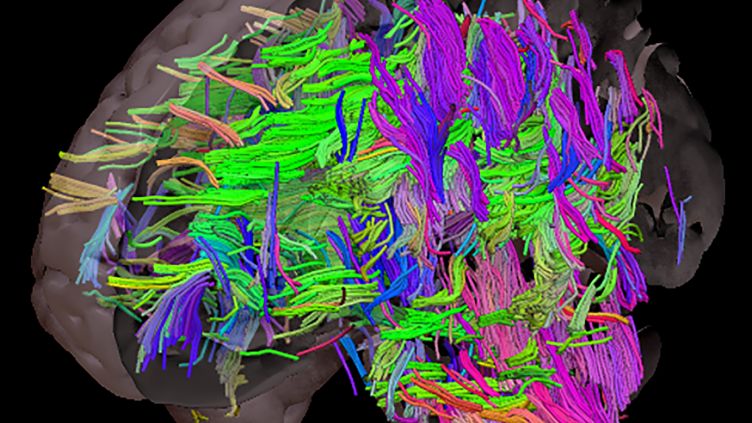

Коннектом мозга: визуализация связей и нейронных путей